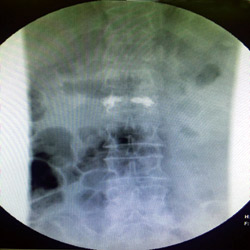

نجح المستشفى السعودي الألماني بالرياض مؤخراً في علاج مريضة في السبعين من عمرها، باستخدام الحقن الأسمنتي للفقرات، كانت تعاني من كسر انضغاطي في الفقرة القطنية ناتج عن هشاشة العظام لديها.

وكان المستشفى استقبل المريضة السبعينية التي كانت تتألم من وجود كسر في الفقرات القطنية، وتم عرضها على د.حازم فريد جراح العمود الفقري الذي وجَّه بعمل الفحوصات اللازمة، والتي أظهرت وجود هشاشة بالعظام، وعلى الفور تم التدخل الجراحي لعمل حقن أسمنتي للفقرة المنضغطة بعد رد الانضغاط؛ وذلك من خلال جرح صغير جداً لا يتعدى 1 سم وعلى أثرها غادرت المريضة في نفس اليوم بعد عدة ساعات من إتمام الجراحة وهي بحالة جيدة جداً مع تحسّن ملحوظ بألم الفقرات.